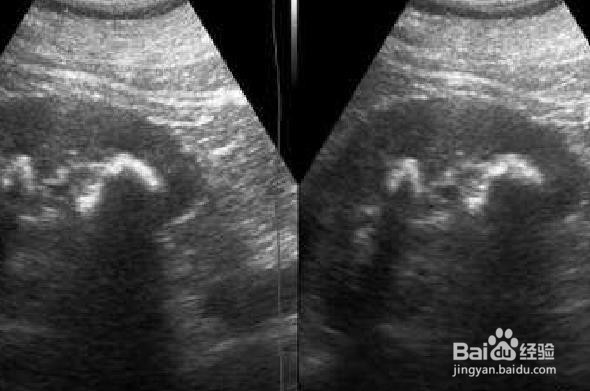

6、 定期超声波

结石形成的过程通常没有明显的症状,只有在结石引起疼痛,尿潴留时才会发现。我们需要花时间进行体检,定期超声检查。然后我们可以检测隐藏在体内的疾病并及时治疗。超声波是一种准确的诊断方法,可以诊断结石的大小和数量。